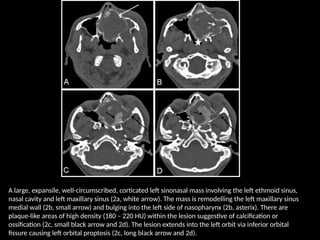

A large, expansile, well-circumscribed, corticated left sinonasal mass involving the left ethmoid sinus,

nasal cavity and left maxillary sinus (2a, white arrow). The mass is remodelling the left maxillary sinus

medial wall (2b, small arrow) and bulging into the left side of nasopharynx (2b, asterix). There are

plaque-like areas of high density (180 – 220 HU) within the lesion suggestive of calcification or

ossification (2c, small black arrow and 2d). The lesion extends into the left orbit via inferior orbital

fissure causing left orbital proptosis (2c, long black arrow and 2d).

AP Skull radiographshows expanded nasal cavity (asterix) with depressed left half of hard palate (short black arrow) and ill-defined left medial orbital wall (black arrow). B: Occipitomental view shows soft tissue opacity occupying the left nasal cavity and left maxillary sinus region with nonvisualized maxillary sinus walls (long black arrow).

• 19.

A large, expansile,well-circumscribed, corticated left sinonasal mass involving the left ethmoid sinus, nasal cavity and left maxillary sinus (2a, white arrow). The mass is remodelling the left maxillary sinus medial wall (2b, small arrow) and bulging into the left side of nasopharynx (2b, asterix). There are plaque-like areas of high density (180 – 220 HU) within the lesion suggestive of calcification or ossification (2c, small black arrow and 2d). The lesion extends into the left orbit via inferior orbital fissure causing left orbital proptosis (2c, long black arrow and 2d).